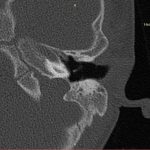

- Diagnosticul traumatismelor de bază de craniu

- Diagnosticul fracturilor:

- Cu înfundare

- Complexe cranio-sinusale

- Complexe cranio-etmoidale

- Complexe cranio-orbitare

- Complexe cranio-faciale